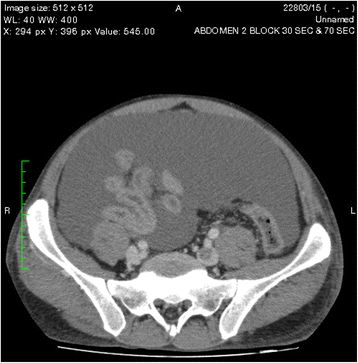

An ultrasound scan of the abdomen showed gross ascites with a normal liver and kidneys. Contrast-enhanced computed tomography (CECT) of the abdomen revealed two pancreatic pseudocysts, measuring 4.5 cm × 3.5 cm and 4.2 cm × 5 cm, respectively, in relation to the pancreatic head (Fig. 1). The pancreatic duct and the rest of the pancreas were normal, without evidence of necrosis or changes of chronic pancreatitis. Gross ascites was visualized on both an ultrasound scan of the abdomen and a CECT scan. The patient’s bowel appeared normal. His peritoneal fluid was an exudate with 4.3 g/dl protein and a serum-to-ascites albumin gradient of −1.1 g/dl (<1.1 g/dl), a lactic acid dehydrogenase level of 527 U/L, WBC of 73 cells/mm3 with 90 % lymphocytes, and RBC of 1.6 × 109/mm3. His ascitic fluid amylase level was high at 3618 IU/L. No malignant cells were seen, and the patient’s Gram stain and acid-fast bacilli smear results were negative, with the culture remaining sterile. His adenosine deaminase level was normal (12 IU/L).

One of the pseudocysts in the head of the pancreas was compressing the inferior vena cava (IVC), as shown in the CECT scans in Figs. 2, 3 and 4. There were filling defects in the left common and internal iliac veins and both proximal external iliac veins, suggesting DVT (Figs. 5 and 6). The patient’s IVC was patent. Multiple filling defects were seen in the right lower lobe pulmonary artery and in segmental branches of the left pulmonary artery, compatible with pulmonary embolism (Figs. 7 and 8). The patient’s liver, gallbladder, spleen, kidneys, and adrenal glands were normal. He had bilateral atelectasis of the lung bases with minimal pleural effusions.